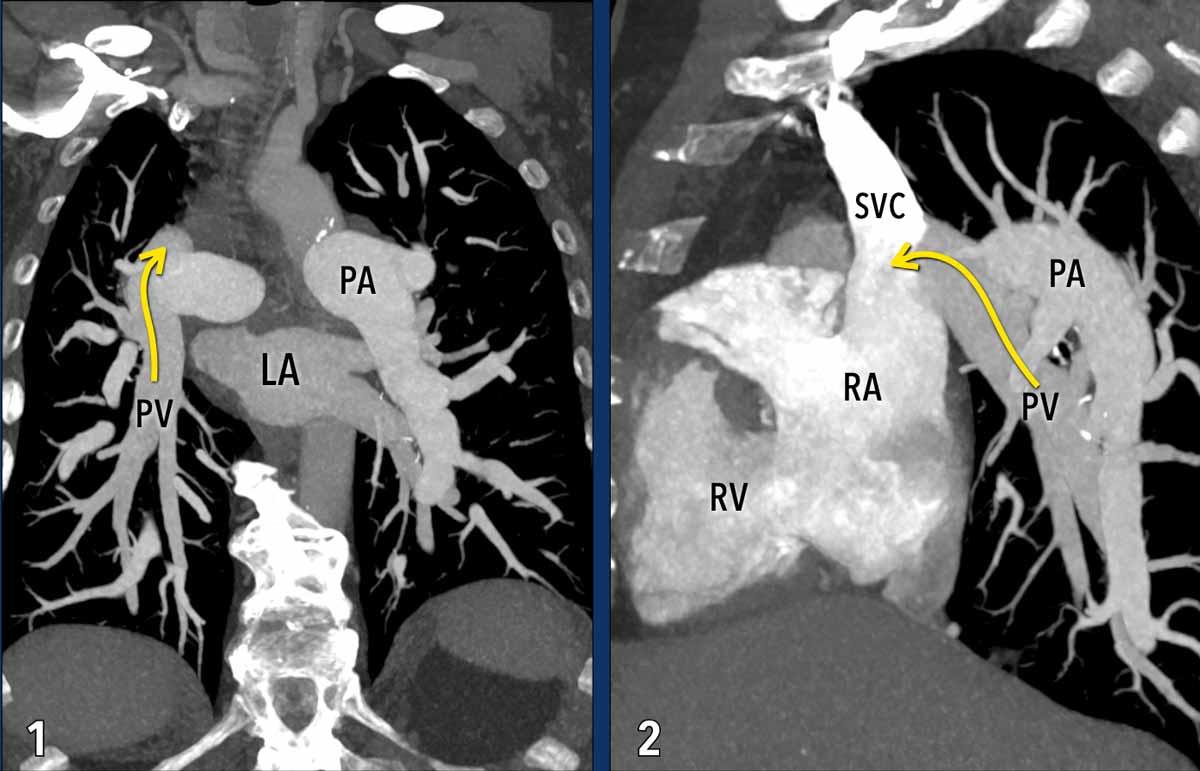

Hồi lưu tĩnh mạch phổi bất thường một phần (PAPVR)

Trong hồi lưu tĩnh mạch phổi bất thường một phần, một hoặc nhiều tĩnh mạch phổi đổ về tuần hoàn tĩnh mạch hệ thống một cách bất thường (chủ yếu vào tĩnh mạch chủ trên ở bên phải, và vào tĩnh mạch tay đầu trái ở bên trái), thay vì đổ về nhĩ trái như bình thường.

Tùy thuộc vào thể tích luồng thông, tình trạng tăng tuần hoàn phổi mạn tính do luồng thông này có thể gây tổn thương nội mô, phì đại cơ trơn và xơ hóa mạch máu, cuối cùng dẫn đến tăng sức cản mạch phổi và hình thành tăng áp phổi.

Minh họa

Trong trường hợp này, hầu hết các tĩnh mạch phổi đổ về nhĩ trái theo đường bình thường (mũi tên xanh).

Tuy nhiên, tĩnh mạch phổi thùy trên phổi phải đi theo đường bất thường và đổ qua tĩnh mạch chủ trên vào nhĩ phải thay vì nhĩ trái (mũi tên đỏ).

Hồi lưu tĩnh mạch bất thường này tạo ra luồng thông trái-phải, dẫn đến tình trạng quá tải thể tích của nhĩ phải và thất phải.

Các hình ảnh này thuộc về một bệnh nhân tăng áp phổi thứ phát do hồi lưu tĩnh mạch phổi bất thường một phần (PAPVR).

Đặc điểm hình ảnh

Các tĩnh mạch phổi thùy dưới phổi phải không kết nối với nhĩ trái (LA) mà thay vào đó đổ vào tĩnh mạch chủ trên (mũi tên).

Lưu ý tình trạng giãn hai bên của các động mạch phổi, phù hợp với tăng áp lực động mạch phổi.